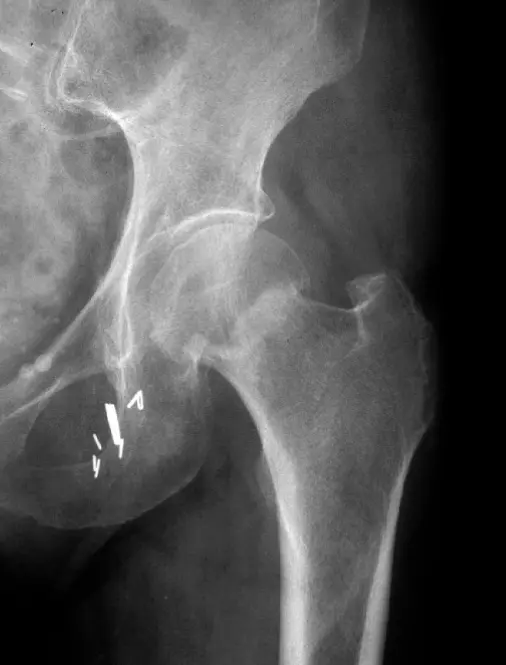

- x-ray of male pelvis and proximal femur, AP view, mature bone fracture in greater trochanter in right side, fracture in neck of femur on left side

pelvis disconounty of cortex indicating fracture in neck of right femur #CC

- Displaced fracture of proximal femur with osteolytic lesion